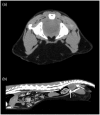

Case summary: A 4-year-old neutered male cat was presented with a 2-month history of intermittent constipation that progressed to obstipation. Primary clinical findings included a large, multi lobulated mass in the caudodorsal abdomen, peripheral eosinophilia and hyperglobulinemia. Abdominal imaging revealed a multilobulated, cavitated mass in the sublumbar region. Exploratory celiotomy revealed multiple firm masses in the sublumbar retroperitoneal space causing ventral displacement and compression of the descending colon with extension of the masses into the pelvic canal. Histopathology was consistent with feline gastrointestinal eosinophilic sclerosing fibroplasia (FGESF). Aerobic culture was positive for Staphylococcus aureus. The cat was treated with prednisolone (2 mg/kg PO q24h), lactulose (0.5 g/kg PO q8h), amoxicillin/clavulanic acid (62.5 mg/cat PO q12h for 1 month) and fenbendazole (50 mg/kg PO q24h for 5 days). Six months postoperatively, the cat had no recurrence of clinical signs. Repeat evaluation and imaging at day 732 postoperatively revealed marked improvement of the abdominal mass, resolution of peripheral eosinophilia and no clinical signs with continued prednisolone therapy (0.5 mg/kg PO q24h).

Relevance and novel information: This is a report of a primary extramural FGESF lesion, and the first description of characteristics of FGESF on CT. Previous evidence suggests that the most favorable outcomes require immunosuppressive therapy and complete surgical excision; however, this case demonstrates a favorable outcome with medical management alone.